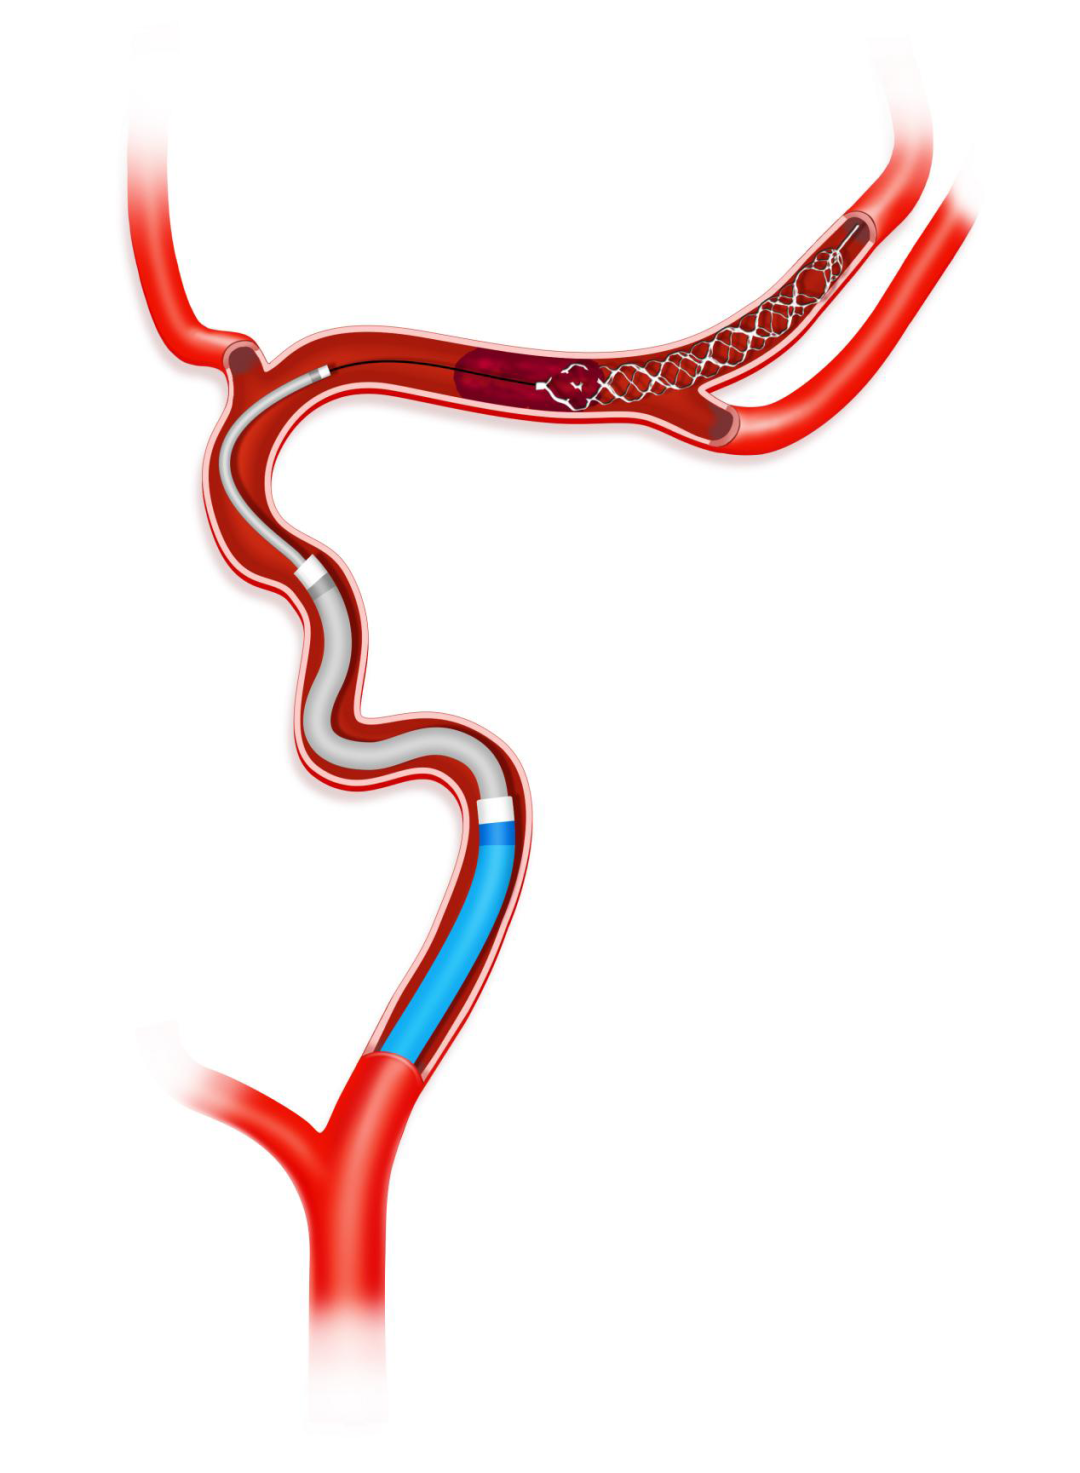

Syphonet®取栓支架锚定作用下跟进Tethys AS®血栓抽吸导管,靠近血管病变处开始关掉滴注,打开血栓抽吸导管Y阀后,越过大脑中动脉闭塞处到达大脑中动脉M1段末端。

负压下将Syphonet®取栓支架撤回Tethys AS®血栓抽吸导管内。